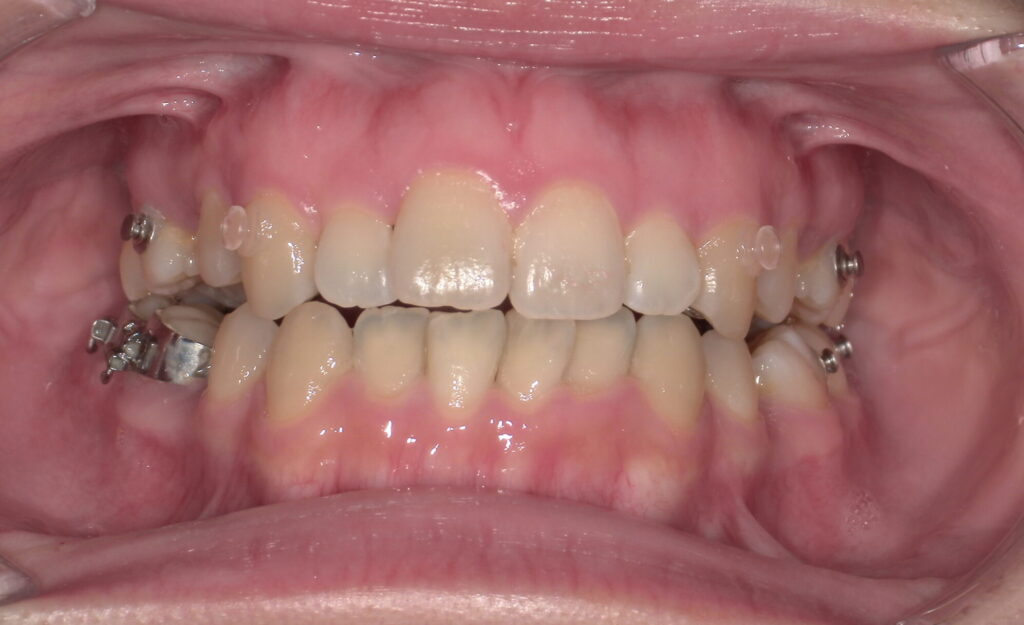

📸治療経過写真

当院で裏側矯正治療しているスタッフの経過写真をご参考にしてください。

上下左右小臼歯を1本ずつ計4本抜歯して現在も治療中です。「歯を抜いた隙間が閉じた量」、「前歯の移動量」、「正面から見た前歯の位置」に注目して見てもらえると、歯の移動の早さが目に見えて分かるかと思います。

約4か月後

正面

(ゴムかけをして奥歯の咬み合わせや出っ歯の治療をするため、何か所かボタンが付いています)